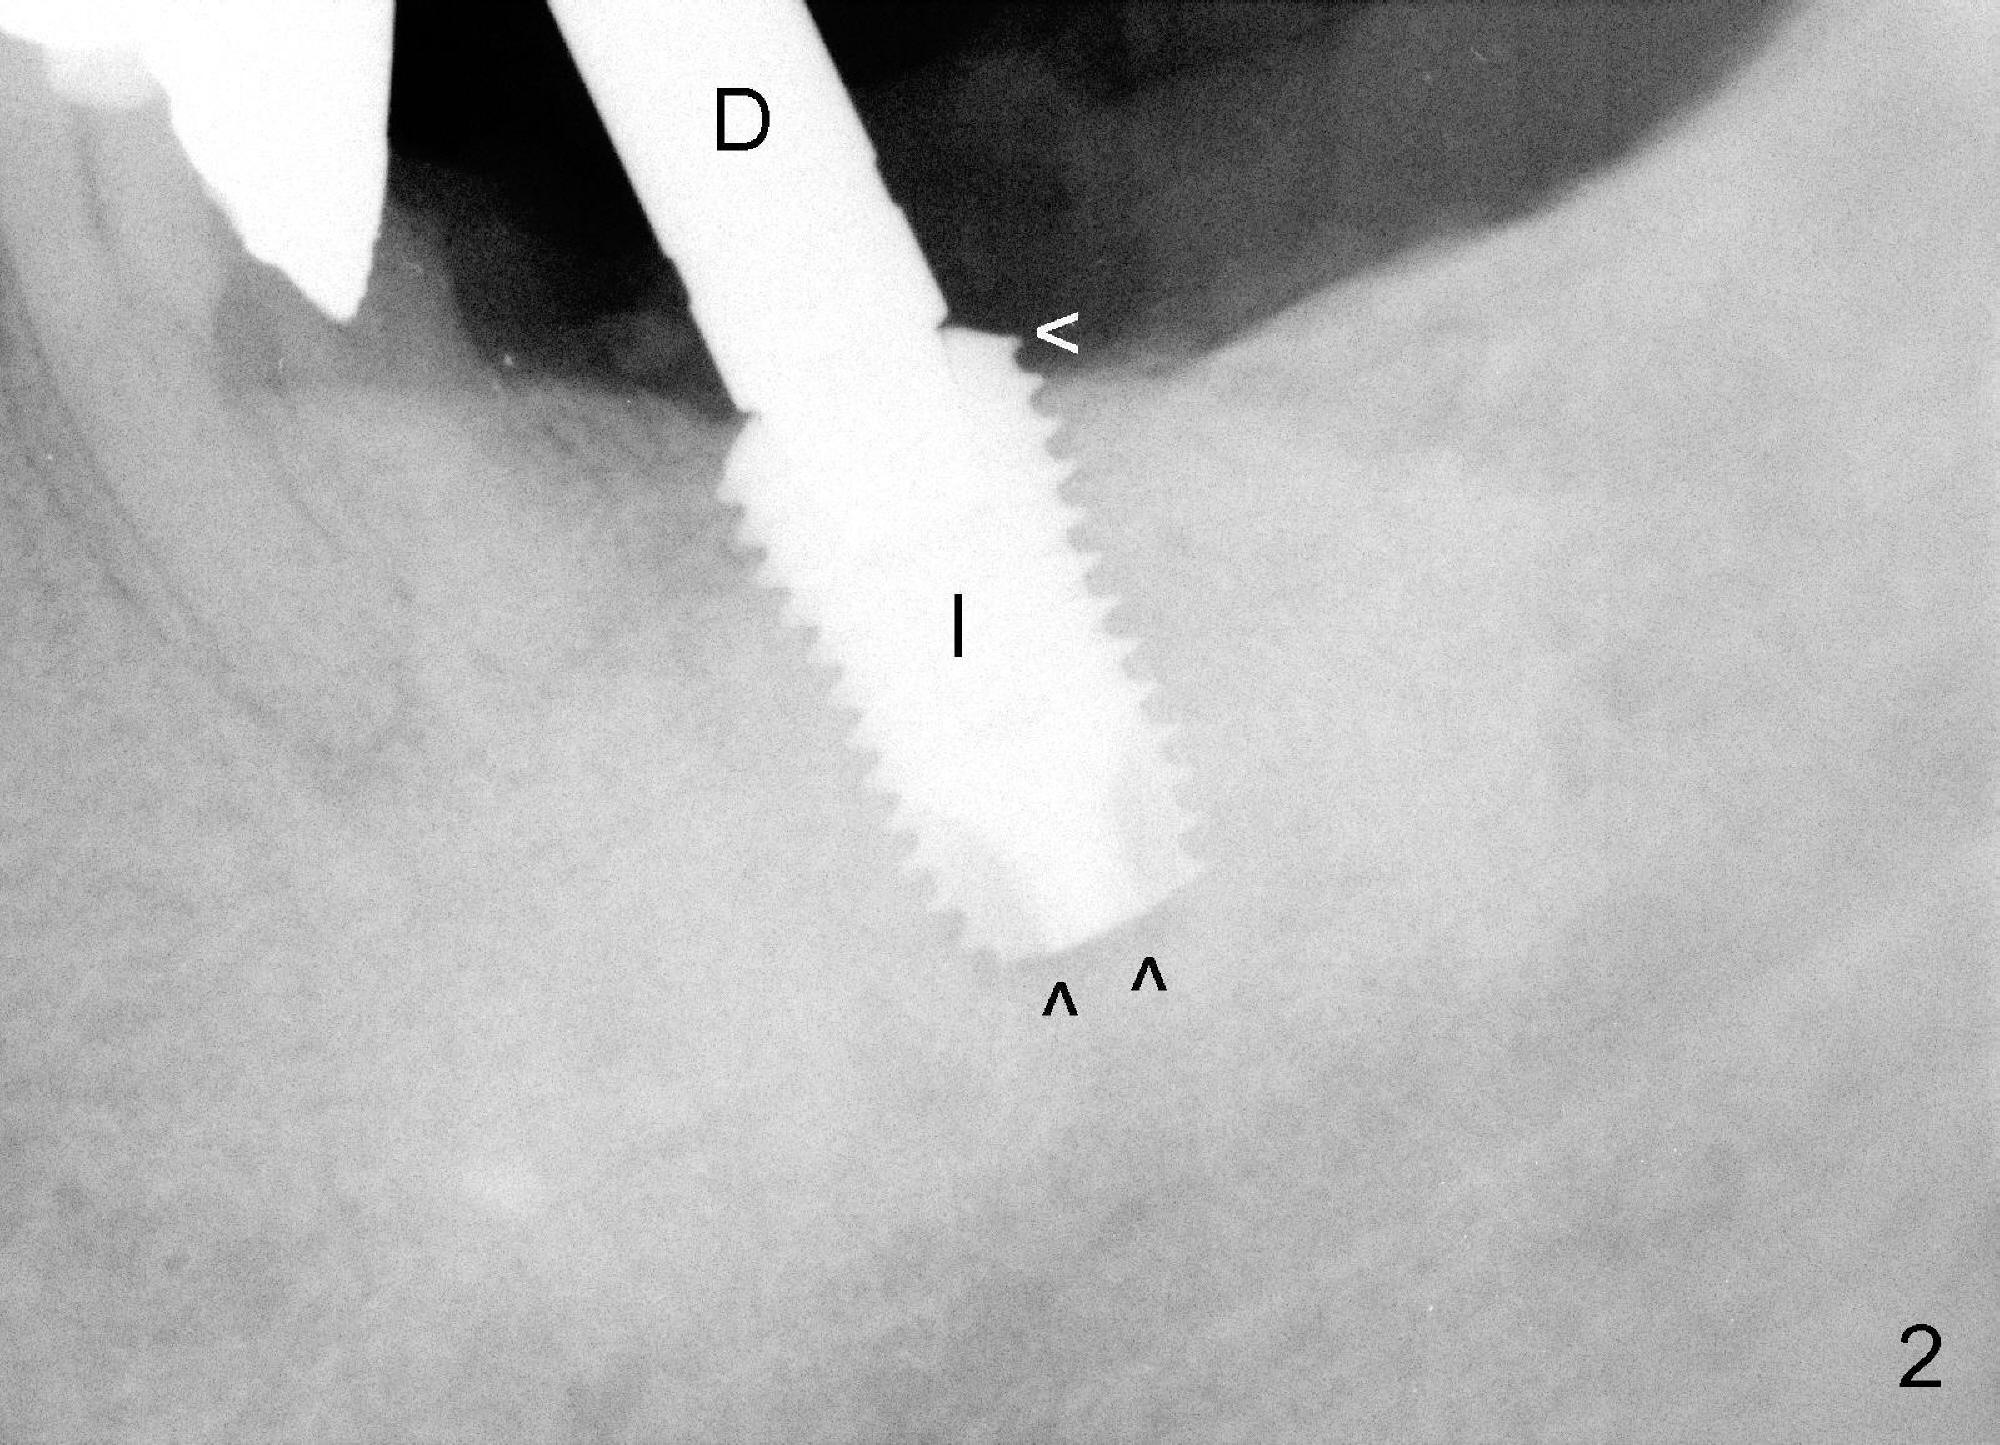

The 69-year-old male is a dental phobic with poor dentition. He wants to an implant at the site of #18 first and refuses to have the tooth #11 (with asymptomatic apical abscess) extracted. To reduce chance of post-implant infection, the implant is placed in a two stage manner. The distal amalgam overhang of the tooth #19 is removed by Piezo scaler (Fig.1). An incision is made. After a 2 mm pilot drill, a parallel pin is inserted; it appears that the coronal end of the trajectory should be leaned mesially (Fig.1 arrow). Since the ridge is wide, an extra wide implant is placed (Fig.2 I: 5.9x10 mm with insertion torque >50 Ncm) with one distal thread exposed (Fig.2,3 <). The disto-occlusal caries of the tooth #20 (Fig.1,4 *) is going to be excavated.

The implant is torqued down further (Fig.5 <, as compared to double ^ in Fig.2). The remaining distal exposed thread is covered by autogenous bone harvested during osteotomy (*). The graft is then covered by collagen dressing, which is held in place by a partially placed healing screw (S). The wound is closed by 4-0 Chromic gut suture and perio glue. The patient is instructed to continue oral Amoxicillin and Chlorhexidine mouth rinse postop.